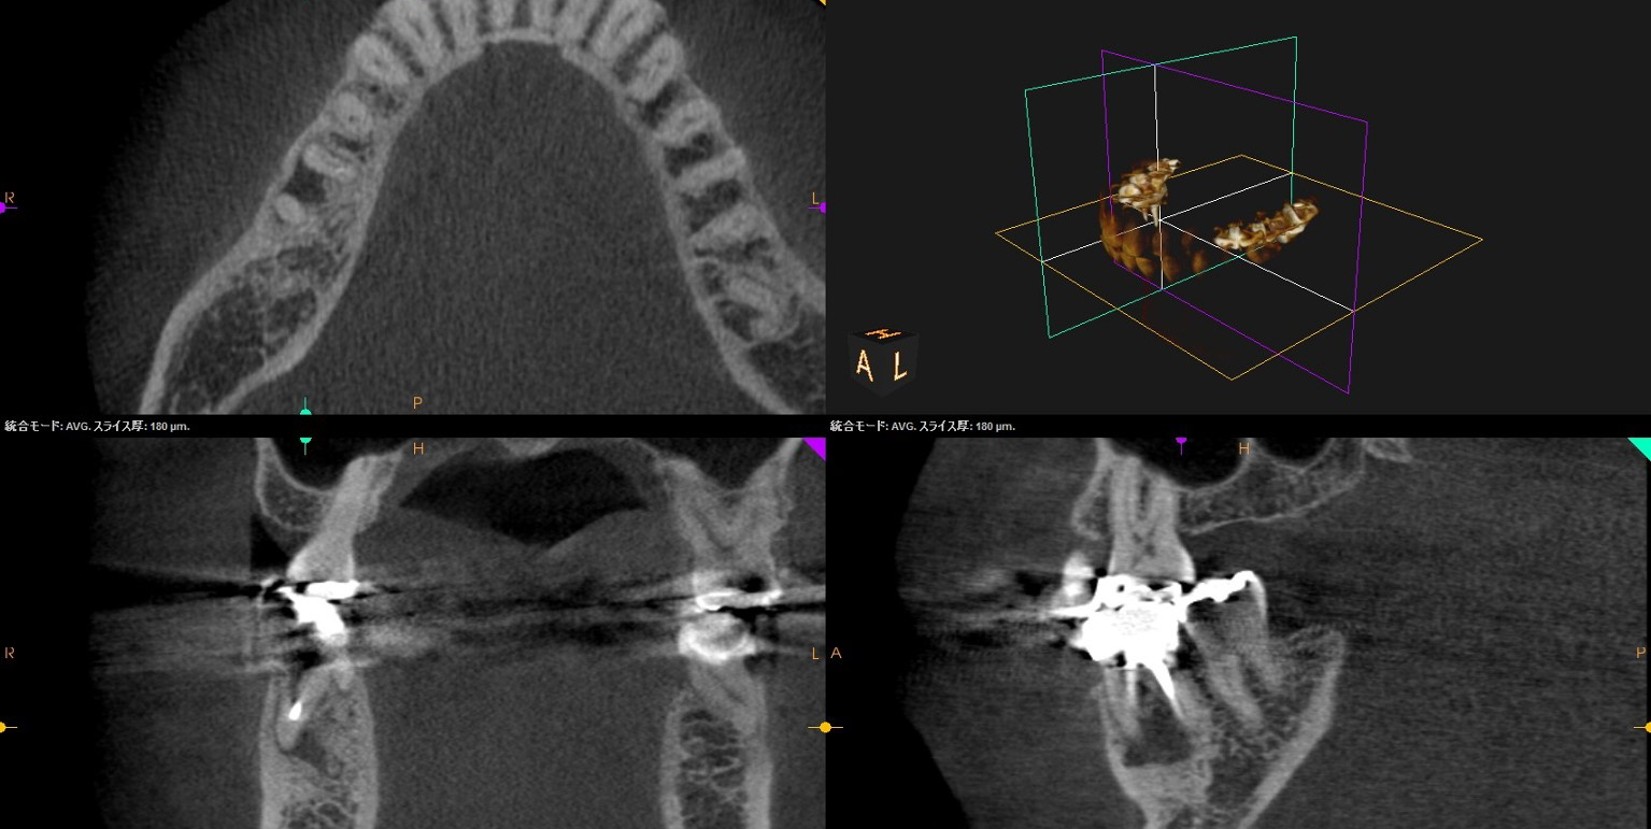

• 初診来院時 根尖性歯周炎により骨吸収あり

• 自費の感染根幹治療終了直後

• 自費感染根幹治療6か月後、骨の回復がみられた

• CT撮影による三次元診断で、見落としのない精密治療